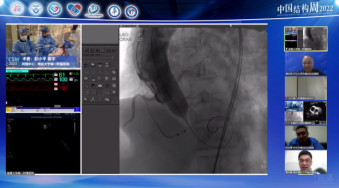

广东省人民医院罗建方教授团队带来一例二尖瓣机械瓣置换术后TAVR手术。由于该患者也存在三尖瓣关闭不全问题,但考虑到右心衰不严重,则优先处理主动脉狭窄问题。术后患者血流动力学稳定,舒张压64mmHg,无瓣周瘘问题。

手术策略:全身麻醉、右股入路、无预扩张、23mm或26mm可回收输送系统。

针对该患者有轻度钙化、瓣环直径21mm,与会专家建议可以预扩,若不行预扩,则先要做好冠脉保护。此外,考虑到患者二尖瓣机械瓣置换术后,本次TAVR手术是否会出现瓣架展开问题,以及是否对机械瓣有影响也是重点关注的内容。对此,参照文献专家建议需注意: